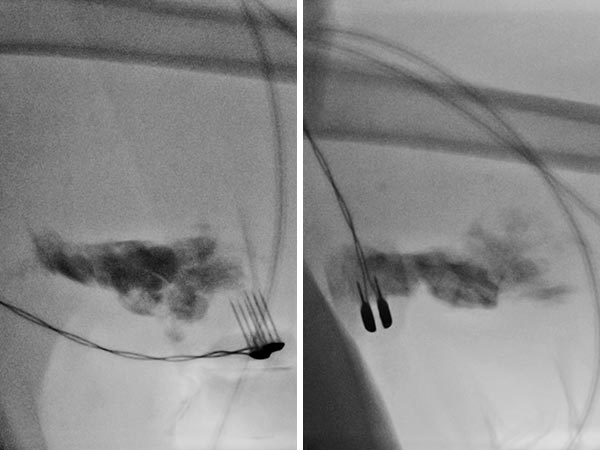

Fluoroscopy during electrosclerotherapy after injection of 0.75 mg bleomycin admixed with 2.5 ml contrast medium into the lymphatic malformation. Application of electric pulses with the finger electrode.